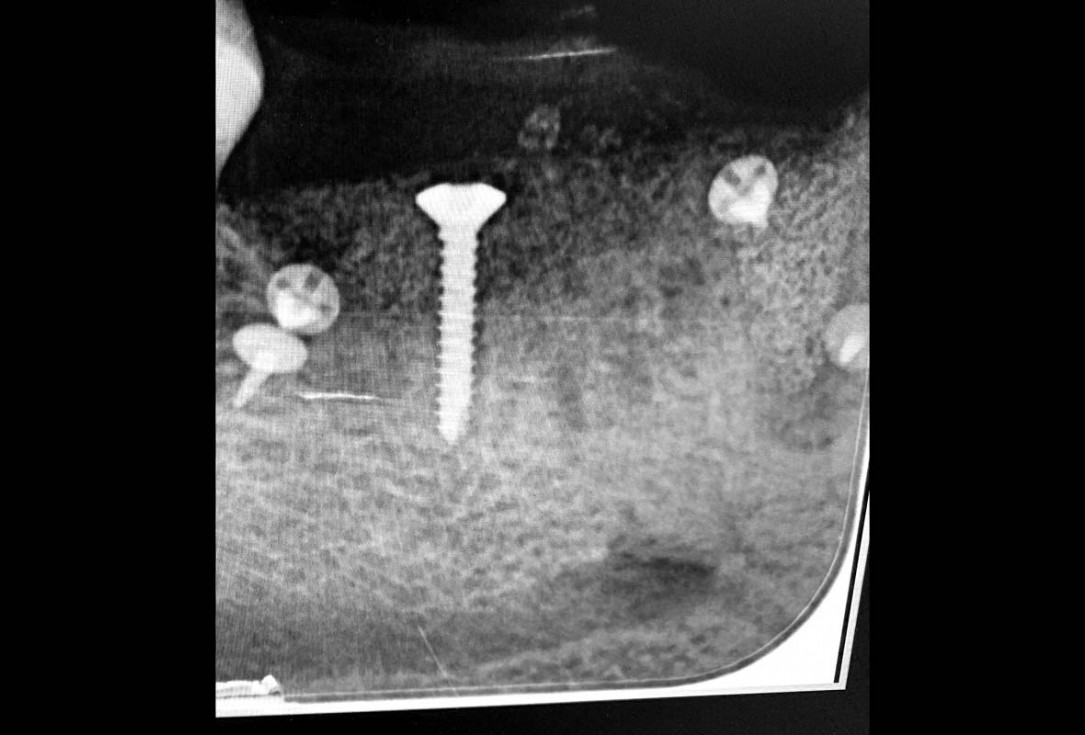

09/29 - Post-operative x-ray controlVertical bone augmentation and broadening of attached gingiva using cerabone®, permamem® and mucoderm® - Dr. R. Naimoli